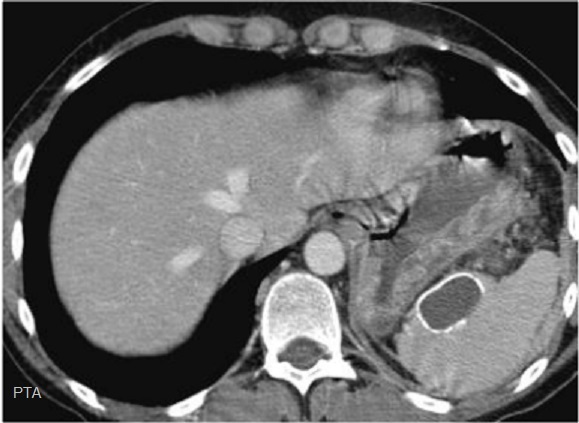

Image

radiologique TDM une rate surnuméraire à petite

taille situe au bord posterieure de la rate ( fléche

raouge ) . Aspect radiologique est une rate petite

homogène a bord nette , lisse , isodensité

retrosplenique |

Une autre cas de rate

surnumeraire avec la rate secondaire a petite taille

pre-splenique ( fléche rouge ) |